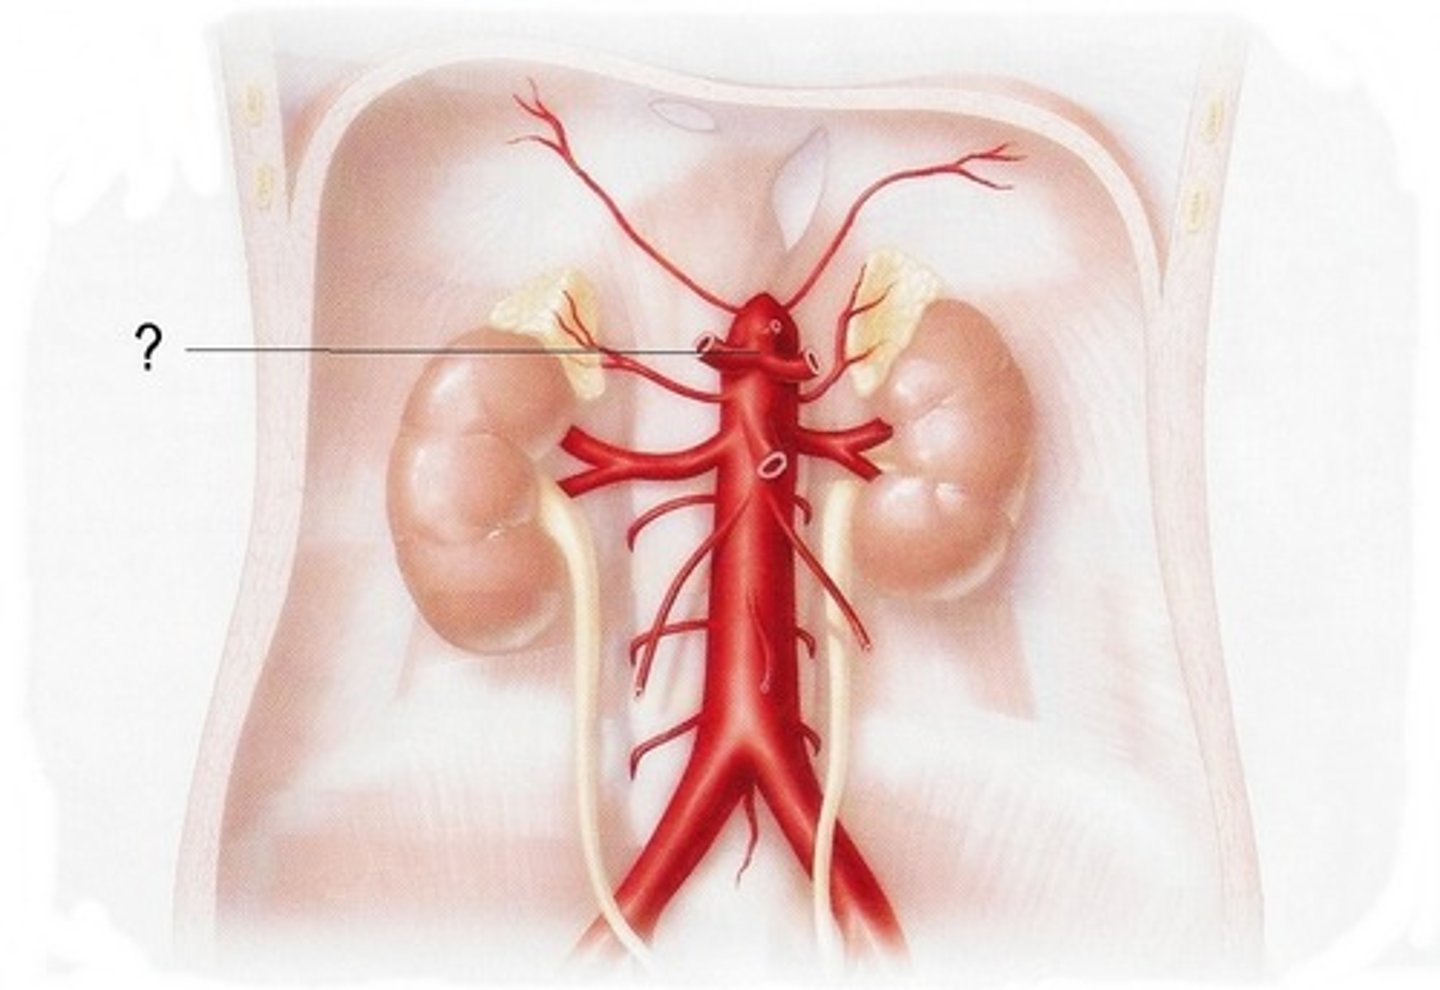

celiac trunk

feeds the splenic artery, left gastric artery, common hepatic artery

superior mesenteric artery

serves the small intestine and ascending and transverse colon

inferior mesenteric artery

serves the transverse and descending colon, sigmoid colon, and rectum

renal artery

serves the kidneys

gonadal artery

serves reproductive organs